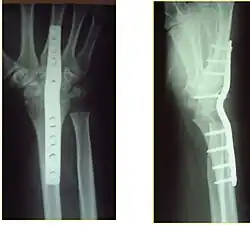

Surgery is generally indicated for displaced or unstable fractures.[18] The techniques of surgical management include open reduction internal fixation (ORIF), external fixation, percutaneous pinning, or some combination of the above. The choice of operative treatment is often determined by the type of fracture, which can be categorized broadly into three groups: partial articular fractures, displaced articular fractures, and metaphyseal unstable extra- or minimal articular fractures.[5]

Significant advances have been made in ORIF treatments. Two newer treatments are fragment-specific fixation and fixed-angle volar plating. These attempt fixation rigid enough to allow almost immediate mobility, in an effort to minimize stiffness and improve ultimate function; no improved final outcome from early mobilization (prior to 6 weeks after surgical fixation) has been shown. Although restoration of radiocarpal alignment is thought to be of obvious importance, the exact amount of angulation, shortening, intra-articular gap/step which impact final function are not exactly known. The alignment of the DRUJ is also important, as this can be a source of a pain and loss of rotation after final healing and maximum recovery.

Surgical options have been shown to be successful in patients with unstable extra-articular or minimal articular distal radius fractures. These options include percutaneous pinning, external fixation, and ORIF using plating. Patients with low functional demand of their wrists can be treated successfully with nonsurgical management; however, in more active and fit patients with fractures that are reducible by closed means, nonbridging external fixation is preferred, as it has less serious complications when compared to other surgical options.[5] The most common complication associated with nonbridging external fixation is pin tract infection, which can be managed with antibiotics and frequent dressing changes, and rarely results in reoperation.[5] The external fixator is placed for 5 to 6 weeks and can be removed in an outpatient setting.[5]

If the fractures are unlikely to be reduced by closed means, open reduction with internal plate fixation is preferred.[5] Although major complications (i.e. tendon injury, fracture collapse, or malunion) result in higher reoperation rates (36.5%) compared to external fixation (6%), ORIF is preferred, as this provides better stability and restoration of the volar tilt.[5][23] Following the operation, a removable splint is placed for 2 weeks, during which time patients should mobilize the wrist as tolerated.[5]